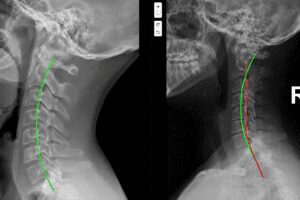

Over the last 15–20 years, chiropractic research — particularly within the Chiropractic BioPhysics® (CBP®) model — has demonstrated that abnormal neck posture, especially loss of cervical lordosis and forward head posture, can place abnormal mechanical and neurological stress on the very structures involved in migraine generation [1][2][3].

When cervical alignment is altered — especially with forward head posture and loss of the normal cervical curve — mechanical stress increases dramatically.

Research has shown that for every inch the head moves forward, the effective load on the cervical spine increases by approximately 10 pounds [6]. Over years or decades, this load changes muscle tone, joint mechanics, nerve signaling, and blood flow regulation.

CBP introduced a higher diagnostic standard by emphasizing:

-

Objective spinal measurements

Postural analysis

Cervical spine radiographic assessment

Comparison to normal spinal alignment models

Repeatable re-examinations

Instead of asking only “Where does it hurt?”, CBP asks:

What is the shape of the cervical spine?

How far forward is the head?

How does this alignment affect neurological stress?

Can this structure be corrected?

What she also had — though no one had ever measured it — was significant cervical spine misalignment and loss of lordosis.

Using CBP protocols, we began gradual, corrective care aimed at restoring the normal curve in her neck.